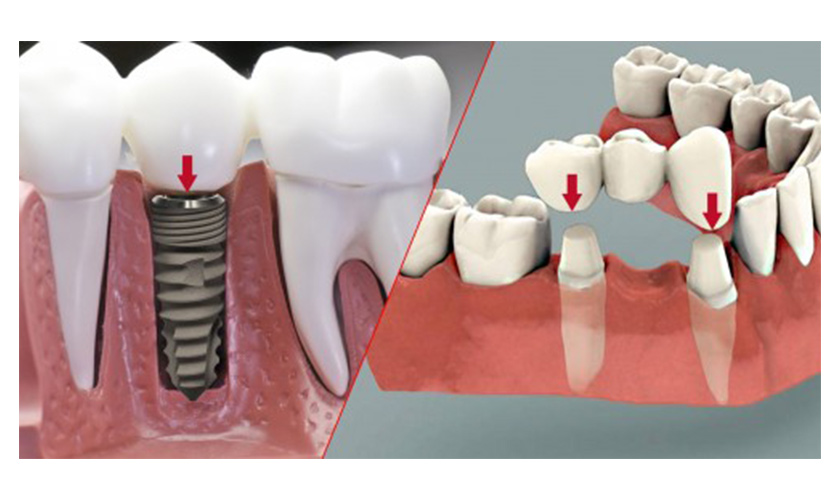

Bảo tồn răng thật xung quanh

So với phương pháp làm cầu răng giả phải mài răng hai bên làm trụ đỡ và đeo hàm giả tháo lắp những móc kim loại có thể ảnh hưởng đến những răng thật xung quanh, thì phương pháp trồng răng Implant được phát triển hơn để không phải tác động gì đến những răng xung quanh.

Điều đó giúp cho bạn bảo tồn răng thật còn lại trong khuôn hàm hoạt động một cách tốt nhất. Cấy ghép Implant là phương pháp không chỉ giúp bạn khôi phục răng mất cách hiệu quả. Nó còn giúp răng thật xung quanh tránh được những tổn thương.